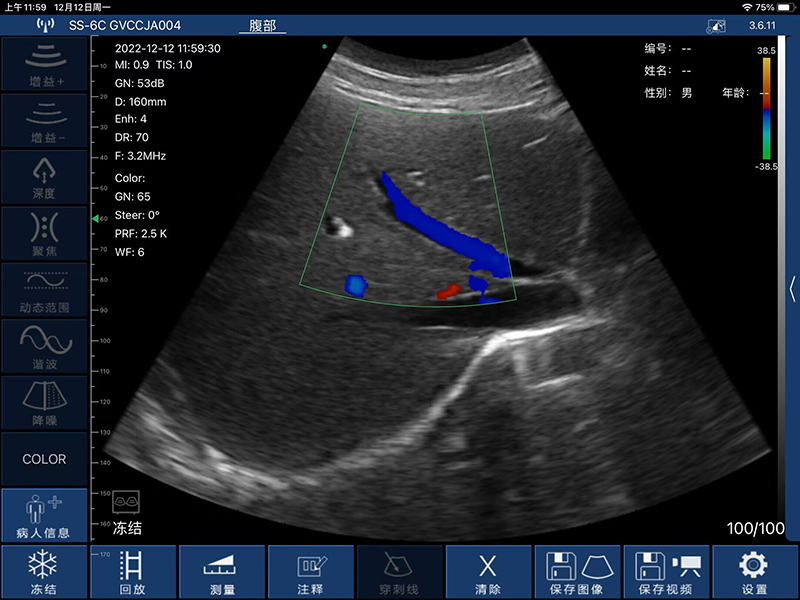

- 显示模式:B、B/M、Color、PW、PDI

- 扫描深度:90/160/240/305mm,可调